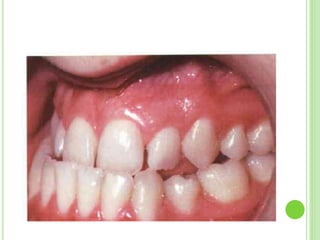

INCISOR RELATIONSHIP

 Class III incisor relationship (The lower incisor edges lie anterior to

the cingulum plateau of the upper central incisors)

 In mild cases , the incisors meet in an edge to edge relationship , when

there may be an anterior mandibular displacement to obtain a

posterior occlusion .This exaggerates the class III incisor relationship.

 In more severe cases , there is an appreciable reverse overjet with

normal path of closure.